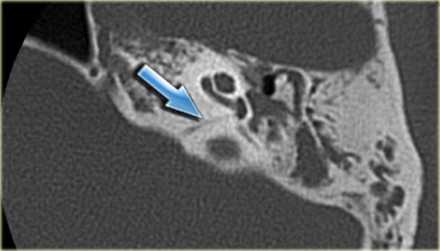

Более точно установить диагноз «невринома слухового нерва» помогает рентгенография и методы нейровизуализации. На ранних стадиях при малых размерах невриномы (до 1 см) она, как правило, не визуализируется при помощи КТ головного мозга. Поэтому проводят рентгенографию черепа с прицельным снимком височной кости. В подтверждение диагноза вестибулярной шванномы свидетельствует расширение внутреннего слухового прохода. Поскольку невриномы хорошо поглощают контраст, возможно использование КТ с контрастированием. При этом визуализируется образование с четкими гладкими контурами.

КТ. Водопровод в норме (стрелка).